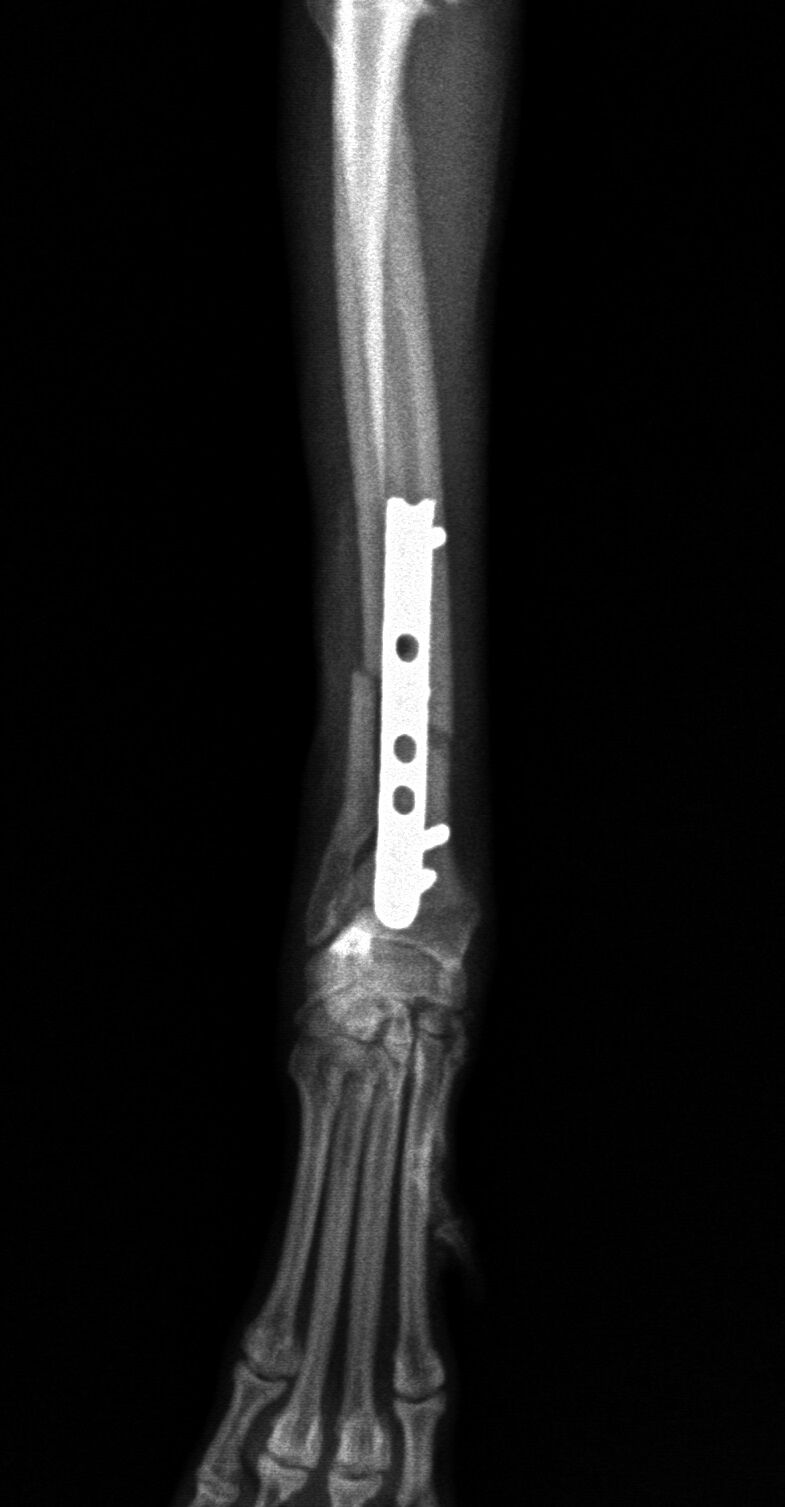

手術後1か月は外固定で補助します。その後、レントゲンで問題ないことを確認し外固定を外しました。外した後は普通に歩行し、散歩なども普段通りにしてもらいます。獣医師によってはプレートを残したままにすることがありますが、中にはプレート部分の骨が細くなってしまうことがあります。もし仮にプレートが折れてしまった時には大変な手術が必要になることがあります。当院では高齢犬であればプレートを残したままにするのですが、この症例は若かったので上記の心配もありますので、プレートを除去することにしました。ただトイ・プードルは骨の増生が良くないことが多いので、プレートを外した直後に再骨折したということがよくあります。ですので、当院ではプレートを留めているスクリューを段階的に外していきます。下の写真は手術後3か月の時に一部のスクリューを取った写真です。

スクリュー除去前 骨折面は消えています。

スクリュー除去後